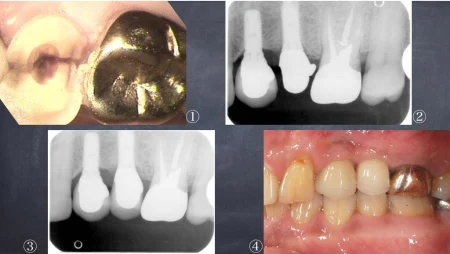

60代男性「奥歯が噛むと痛い」割れて残せない歯を、人工の土台を埋めて歯を取り付ける「インプラント治療」で補い、しっかり噛めるようにした症例

拝見したところ左上の奥歯(第2小臼歯/5番)の歯ぐきから出血しており、詳しい検査で歯が割れていることが確認できました。

割れてしまった歯は耐久性が無いため、被せ物などで治療することは難しく、抜歯が必要と診断しました。

まず割れた歯を抜き、3週間後にインプラントを埋める手術を行いました。

インプラントとあごの骨が定着した後、人工の歯を取り付けて噛み合わせを回復しました。

しっかり噛めるようになり、見た目も自然な仕上がりになりました。